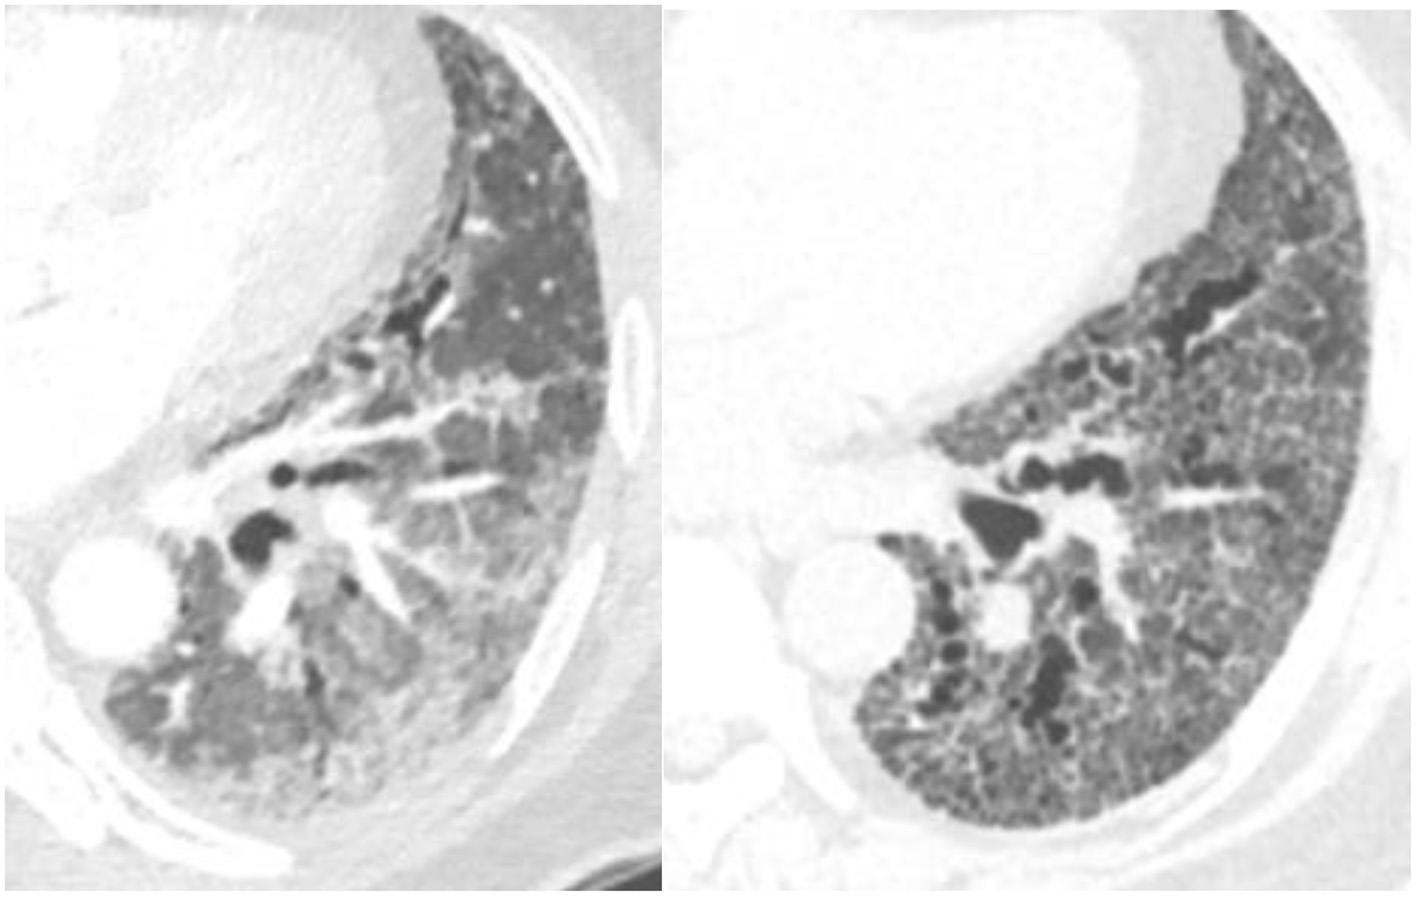

NSIP is a homogeneous, lower lung predominant type of fibrosis typically associated with connective tissue disease (CTD) (25). People with an NSIP pattern are more likely to be younger, and female gender (13). It has an overall better prognosis with fewer exacerbations compared to UIP (26), the median survival is >9 years (13). The extent of disease can be measured visually and progression noted when the extent of normal lung decreases. The radiologists can also describe the progression from non-fibrotic cellular NSIP with its predominant ground-glass opacity to mixed cellular and fibrotic NSIP with ground glass opacities and bronchiectasis and eventually fibrotic NSIP with the resolution of the majority of ground glass and addition of honeycombing in some patients (Figure 3). In a study of 108 patients with a working diagnosis of CTD, the radiographic pattern of disease changed over time in 35%. Sixty-three percent of patients had increased extent of disease on CT over time (26). The progression from a cellular phenotype to fibrosis is an important radiographic observation and along with patients clinical status can define a progressive phenotype.

Figure 3

Evolution of scleroderma from a cellular NSIP pattern to a mixed cellular and fibrotic pattern with bronchiectasis over the course of 10 months consistent with progressive disease.